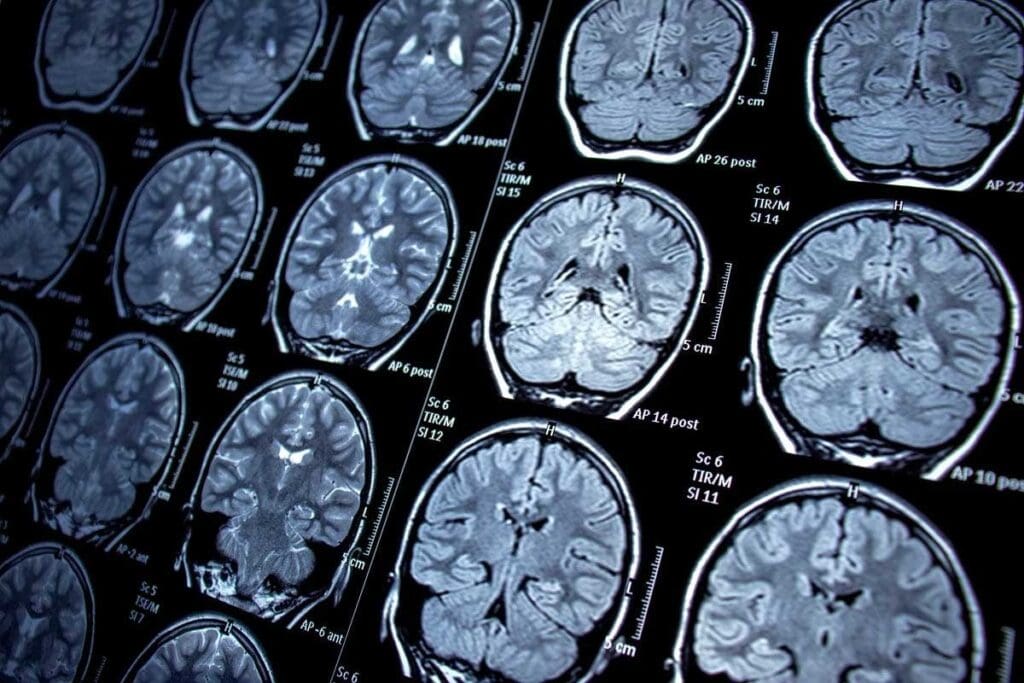

Diagnostic Imaging Techniques

Imaging tests are vital for finding and figuring out brain tumors. The main ones are:

- Magnetic Resonance Imaging (MRI): Gives detailed brain pictures and is great for soft tissue.

- Computed Tomography (CT) scans: Good for quick checks in emergencies and spotting big tumors or bleeding.

These tests help doctors see how big the tumor is, where it is, and how it might affect the brain.